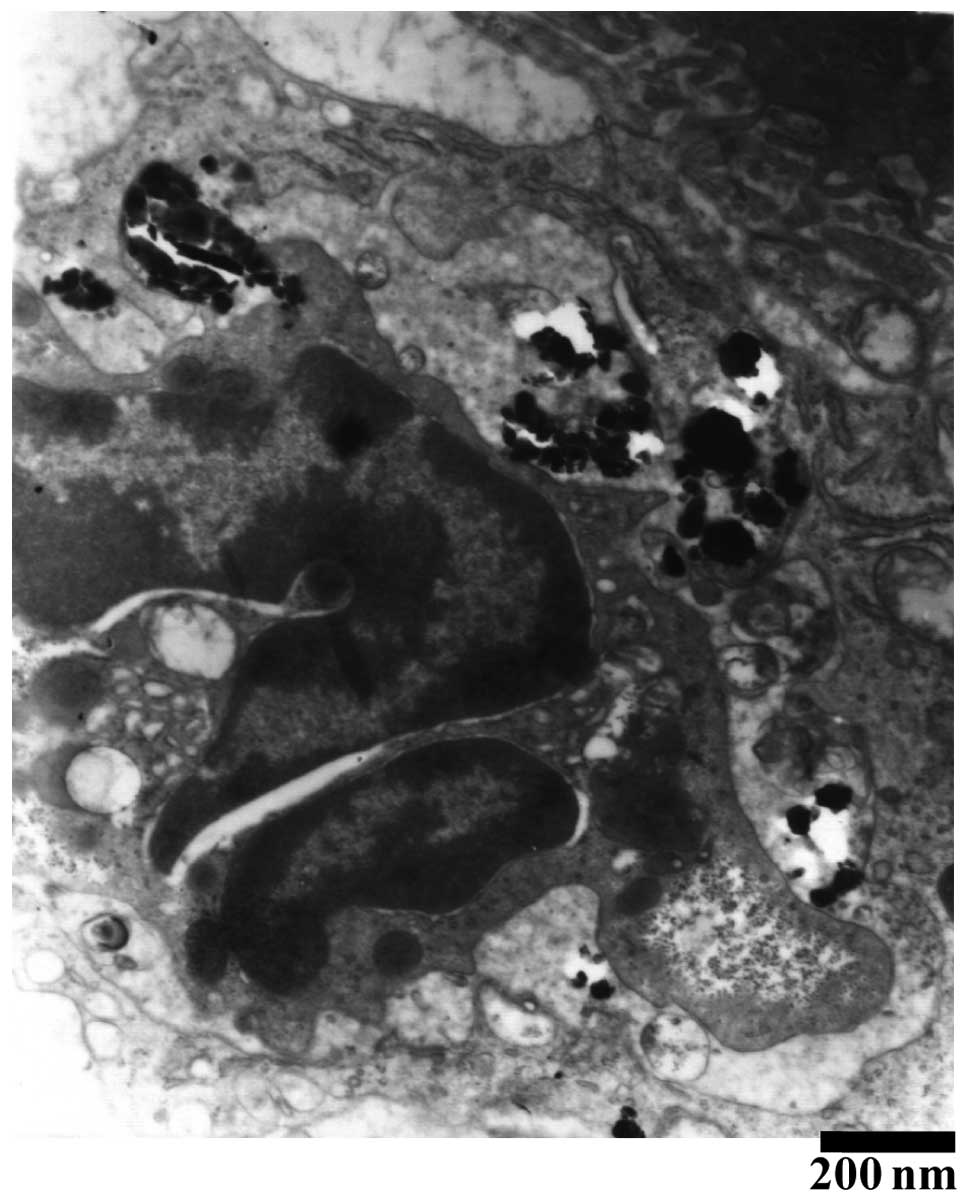

Additionally, as shown in Fig. 2 for group B, 2 h following the intravenous Nano-HA administration, no marked changes to the gross tissue anatomy were identified in the liver. One day later, small irregular nodules composed of neogenetic hepatic lobules emerged on the liver surfaces, while hepatic cells were slightly stained with a vesicular, pale and watery cytoplasm. The hepatic vesicular contents evidently decreased in the following two days and returned to normal two weeks following the intravenous Nano-HA administration. In addition, as shown in Fig. 3, a large quantity of refracting crystal granules were detected within the Kupffer cells ≥24 h following the Nano-HA intravenous injection.

Figure 3

A large quantity of refracting crystal granules were detected by electron microscopy within the Kupffer cells ≥24 h following the nano-hydroxyapatite intravenous injection.